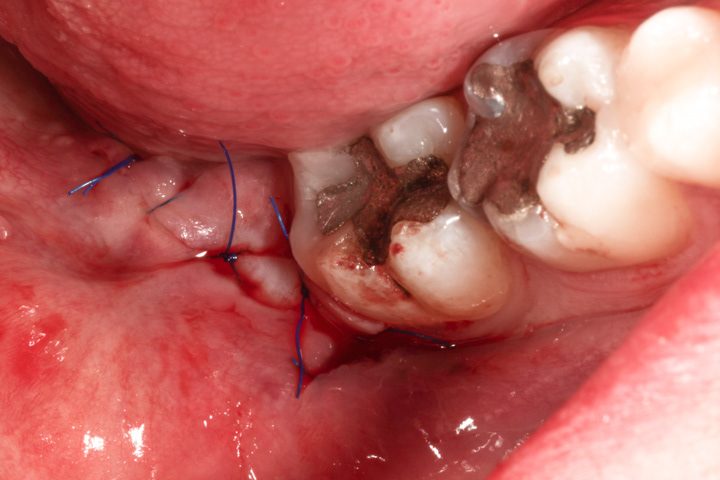

"Czy należy usuwać zęby mądrości?"- to często pojawiające się w gabinecie stomatologicznym pytanie. Każdy przypadek warto rozważyć indywidualnie, ale w większości odpowiedź brzmi: "tak". Wynika to z faktu, że ósemki często generują problemy samą swoją obecnością w jamie ustnej- niekoniecznie dlatego, że są popsute. U wielu osób zdarza się, że po prostu brakuje przestrzeni w szczęce lub żuchwie, dla prawidłowego wyżynania się i pozycjonowania tych zębów. W tym wypadku ósemki górne wrastają w policzki, a dolne blokują się pomiędzy kątem żuchwy a siódemkami dolnymi. Powoduje to po pierwsze, że zęby te generują znaczne siły działające na zęby sąsiednie często prowadząc do zniszczenia ich korzeni. Ponieważ dzieje się to w kości czasem trudno pacjentowi w porę wyczuć ten problem i dochodzi do utraty bardzo istotnych zębów nr 7. Po drugie może utrudniać higienizację ósemek, ale i siódemek co prowadzi do szybko rozwijającej się próchnicy. Po trzecie może prowadzić do stłoczenia zębów lub wykrzywiania ich w całym łuku zębowym. Kolejnym problemem może być często pojawiający się bolesny stan zapalny dziąsła- ponad rosnącą ósemką tworzy się kaptur z błony śluzowej, który zostaje zainfekowany przez zalegające bakterie z resztek pokarmowych. Nieprawidłowa pozycja ósemek sprzyja także przygryzaniu policzków co może prowadzić do powstawania w miejscach urażanych tzw. leukoplakii. Jest to schorzenie objawiające się białym rogowaceniem nabłonka jamy ustnej, a znaczny odsetek tych zmian przekształca się w nowotwór. Kolejnym przykładem na problem generowany pozostawionymi zębami mądrości są tzw. torbiele zawiązkowe powstające na bazie zawiązków tych zębów. Torbiele te nie wykryte w porę, poprzez rozrost, prowadzą do znacznych ubytków kości co grozi złamaniami np żuchwy.

PRZYKŁAD 2